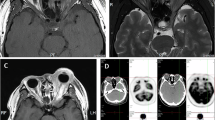

Primary central nervous system lymphoma (PCNSL) is a non-Hodgkin lymphoma involving the brain with possible leptomeningeal and ocular involvement. This study aimed to evaluate the safety and efficacy of modified intravitreal injection regimen of methotrexate (MTX) for therapeutic management of vitreoretinal lymphoma.

Forty human immunodeficiency virus (HIV)–negative Chinese patients with primary vitreoretinal lymphoma were included in this retrospective noncomparative interventional case series study. Patients were treated with a modified protocol of intravitreal injection of MTX (400 µg/0.1 ml) according to the Intensive-Consolidation-Maintenance regimen. The Intensive phase of once-weekly intravitreal injections for 1 month, followed by the Consolidation phase of one injection every 2 weeks for 1 month, and then the Maintenance phase of once monthly for 1 month, for a total of 7 injections. The primary main outcome measures were clinical response to intravitreal chemotherapy, number of injections for clinical remission, progression-free survival (PFS), overall survival (OS), visual acuity (VA), complications during the study period, and cause of death were investigated.

The duration of follow-up from the commencement of injection of MTX was 12–73 months (median 28, 30.55 ± 14.73 months). A total of 61 eyes of 40 patients were cleared clinically from malignant cells after a median 6.57 ± 3.12 (median 6, range 1–14) times of injection of MTX. A second remission was induced in 3 patients, who were treated with a further course of intravitreal chemotherapy after tumour recurred in their eyes. The median PFS and OS were 20.82 months (95% CI 14.64–27.01) and 29.29 months (95% CI 16.16–42.41), respectively. Complications that occurred during the period of treatment and follow-up included corneal epitheliopathy (3 of 61 eyes) and cataract (6 of 61 eyes). There were no cases of maculopathy, vitreous haemorrhage, optic atrophy, and sterile endophthalmitis. No patient had an irreversible loss of vision that could be attributed to the intravitreal injection of MTX.

It can be concluded that the modified intravitreal injection regimen of MTX is an effective therapeutic approach in inducing clinical remission of intraocular involvement in PCNSL patients, associated with few complications. However, further study needs to be conducted to indicate whether the proposed approach extends life expectancy.